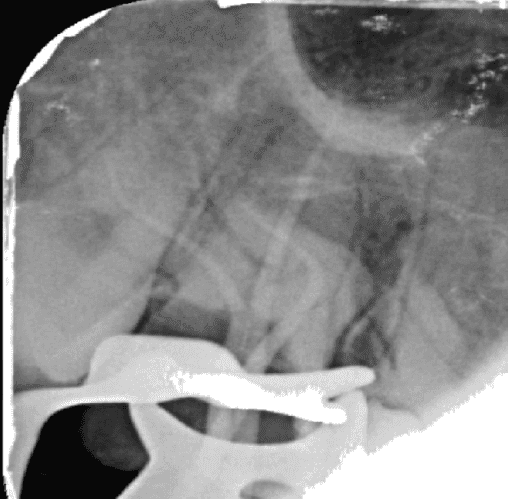

4. Restoratif Aşama (Endokron Uygulaması)

17 numaralı dişteki aşırı koronal madde kaybı ve kırık geçmişi göz önüne alınarak, dişte oluşabilecek kama etkisini (wedging effect) ortadan kaldırmak ve biyomekanik direnci artırmak amacıyla post-core restorasyon yerine Endokron yapımı tercih edilmiştir. Endokron restorasyonu ile pulpa odasının retansiyonundan maksimum düzeyde faydalanılarak dişe monoblok bir yapı kazandırılmıştır.

17 numaralı diş gibi ulaşılması zor ve anatomik olarak yüksek kurvatür riskleri barındıran bir dişte, kök kanal anatomisine saygılı bir preparasyon tekniği ve etkin bir irigasyon protokolü (EDDY) ile tek seans kök kanal tedavisi başarıyla uygulanmıştır. Aşırı madde kaybı olan diş, endokron restorasyonu ile hem biyomekanik hem de fonksiyonel olarak dental arka yeniden kazandırılmıştır.